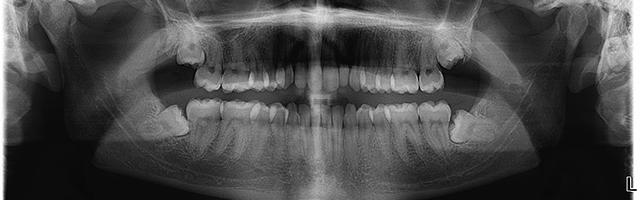

Teeth are subject to decay and damage, and sometimes they get ruined in one go. But more often, there are signs that something bad is going to happen well before tooth decay sets in. Learn what these signs are and prevent tooth decay (or dental caries) from ruining your teeth with a few easy steps.